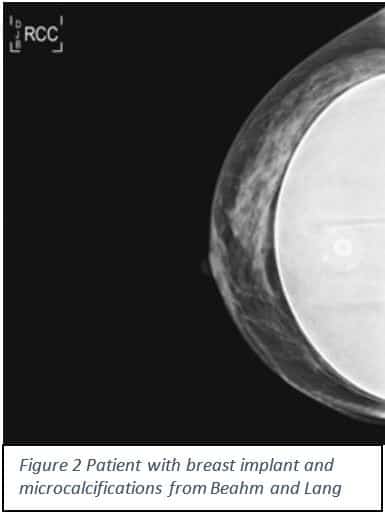

There is an increasing number of patients who elect to have two stage breast reconstruction post mastectomy4. According to the American Society of Plastic Surgeons the incidence of breast reconstruction has increased to over 100,000 a year; and the majority of these cases will be two-stage tissue expander/implant procedures4. Post-reconstruction these patients will need to be monitored to determine if there is a risk of cancer recurrence. How effective is the mammogram at detecting the recurrence of breast cancer when there is a breast implant? Is it any different than the rate of false positives with a breast without an implant?

A mastectomy will remove most of the breast tissue, but the rate of local recurrence in a reconstructed breast is between 5 and 15 %5. According to Kam and colleagues there is were no statistically significant differences between patients with or without implants in regards to cancer detection rate, time to resolution of abnormal imaging, or their BiRads 0 scores (which means a possible abnormality is seen, but more tests are needed)6. Levigne and colleagues compared the cancer mortality rate between patients with breast implants and those with a non-breast cosmetic surgery and found there was no difference in ability to detect and no worse prognosis7. Although Adrada and colleagues found that with a reconstruction patient it is more effective to detect with ultrasound then confirm with an MRI, a much more expensive procedure8. In order to resolve this issue more studies are needed to determine the most accurate and cost effective way to detect any local cancer recurrence early in patients with implants.

10..Beahm, E., and J. Lang. “Breast Cancer: Diagnosis, Therapy, and Oncoplastic Techniques.” Plastic Surgery Key. N.p., n.d. Web. 04 Nov. 2016.